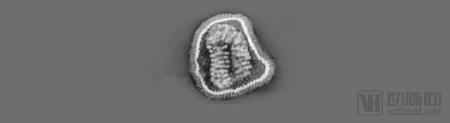

流感病毒颗粒的投射电子显微成像(来源于《流感预测新时代》)